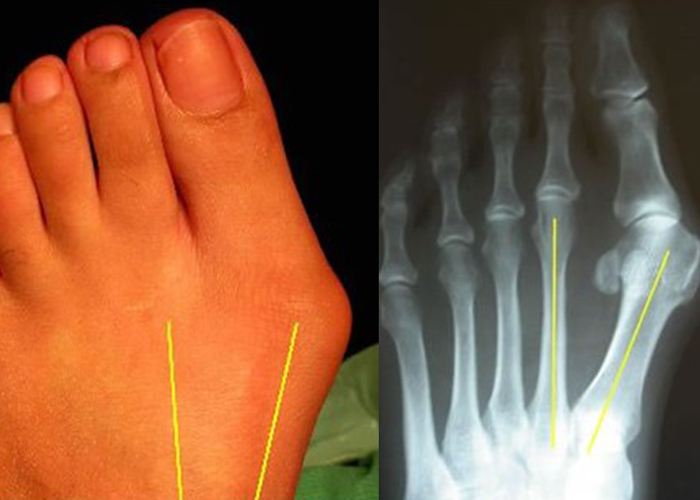

발가락의 형태적인 변형만으로 진단가능하나, 정확한 진단을 위해 방사선 촬영으로 관절 구조와 뼈의 상태를 확인후 정량화 하여 평가합니다.